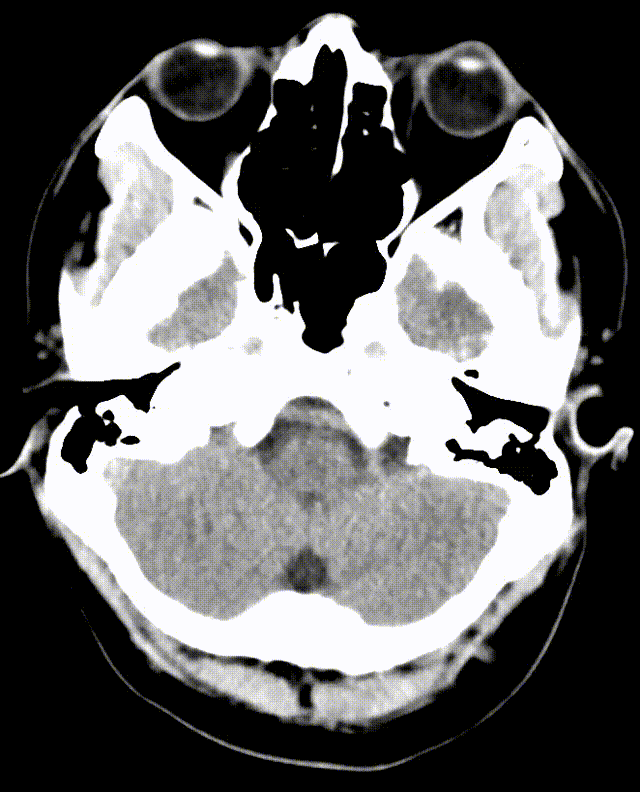

急诊颅脑CT平扫未见异常,必要时MRI检查。

术后复查CT:双侧大脑及小脑半球稍肿胀。

术后MRI:脑干新发梗死。